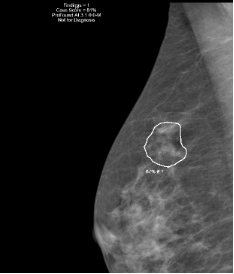

Cancer du sein

Examens d’imagerie médicale

Mammographie avec au besoin en complément échographie, biopsie ou IRM mammaire.

Programme de dépistage cantonal

Mammographie tous les 2 ans chez les femmes de 50 à 74 ans. Medimage est accrédité par la Fondation pour le dépistage du cancer.